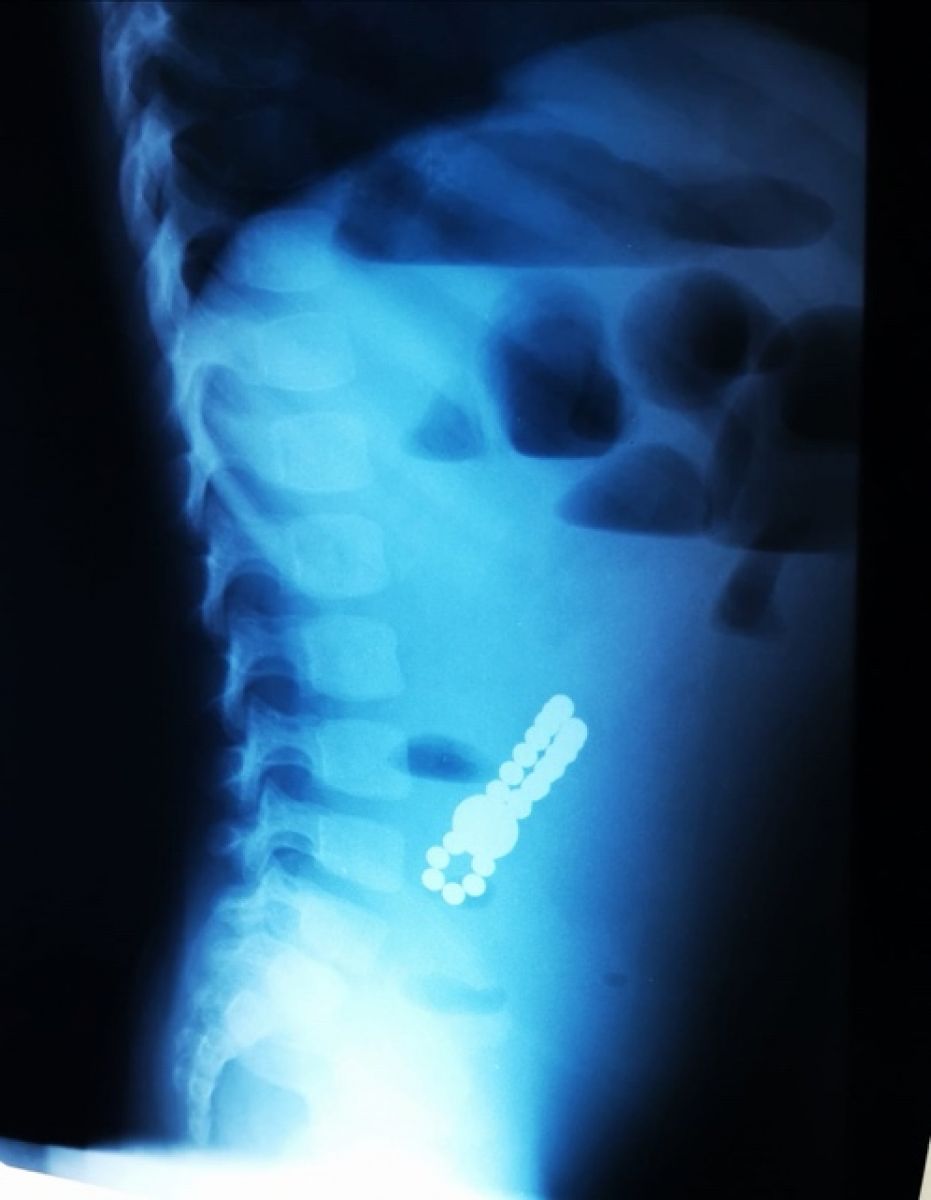

„Acești magneți sunt foarte puternici, iar ingestia lor poate duce la probleme gastrointestinale grave. Odată înghițiți sunt atrași unul spre altul chiar dacă se găsesc în secțiuni diferite ale tubului digestiv. O ansă intestinală prinsă între acești magneți se poate perfora ducând la tratament chirurgical de urgență. În secția noastră, de la începutul anului s-au prezentat trei cazuri, două fete și un băiat, cu vârste cuprinse între 2 și 4 ani. Aceștia au suferit perforații la nivelul intestinului subțire și au necesitat intervenții pentru îndepărtarea porțiunii de intestin afectate”,

dr. Adriana Constantineanu.